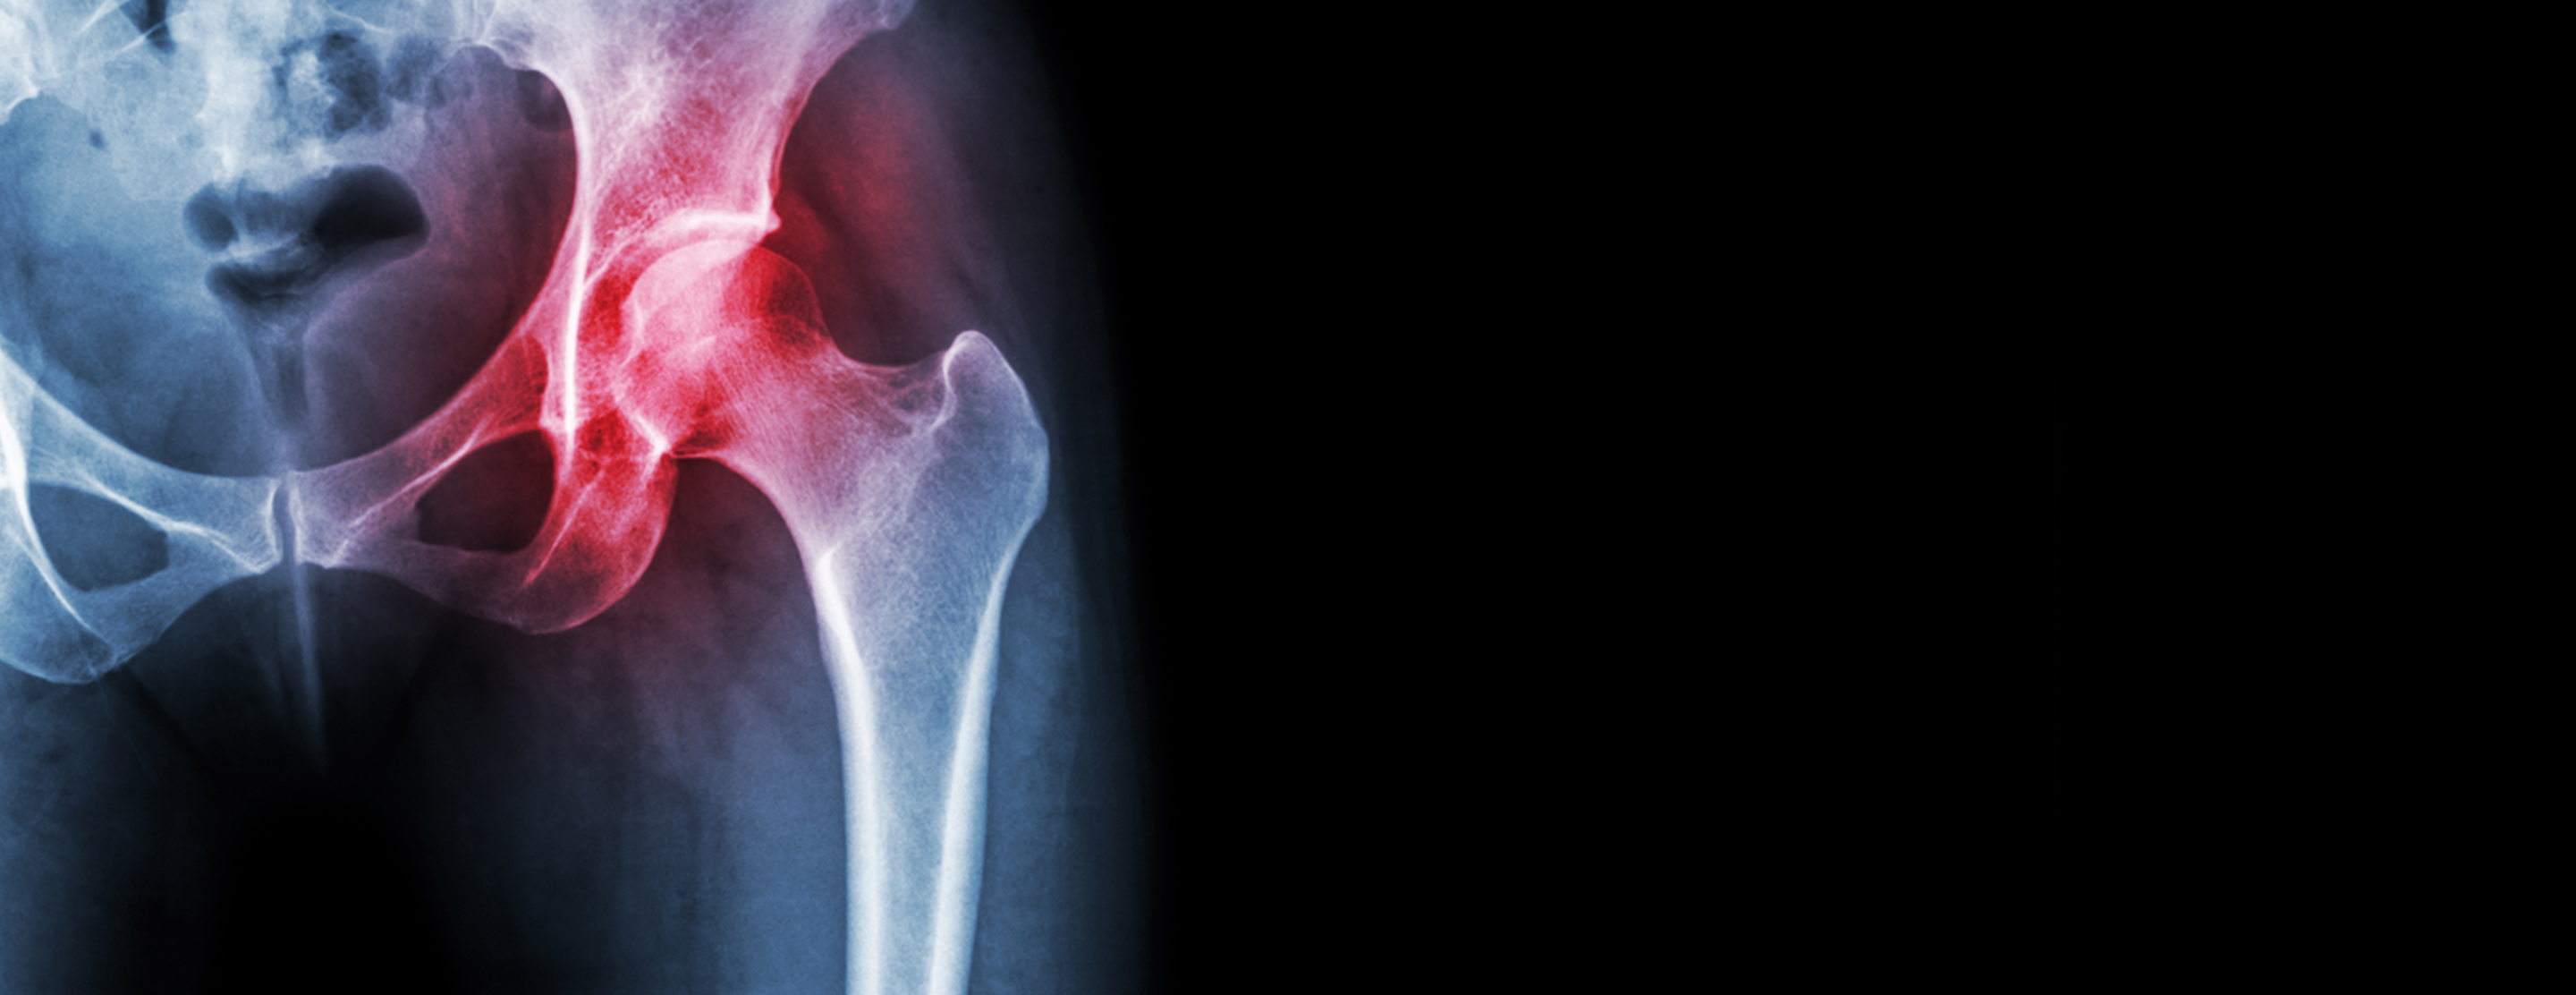

- Hip joint injection

During a joint injection, you will lie on your stomach on an X-ray table. The skin over the targeted joint is cleaned with antiseptic solution and then injected with local anesthetic to numb the area. Using X-ray guidance, the doctor will insert a needle into the targeted joint and inject a combination of anesthetic and steroids.